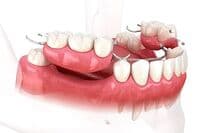

Denture treatment

入れ歯治療

入れ歯は、歯を失った部分を補う取り外し可能な人工の歯です。部分入れ歯と総入れ歯があり、手軽に咀嚼機能を回復できます。外科手術が不要ですが、噛む力が天然歯より劣り、装着時の違和感が生じることもあります。